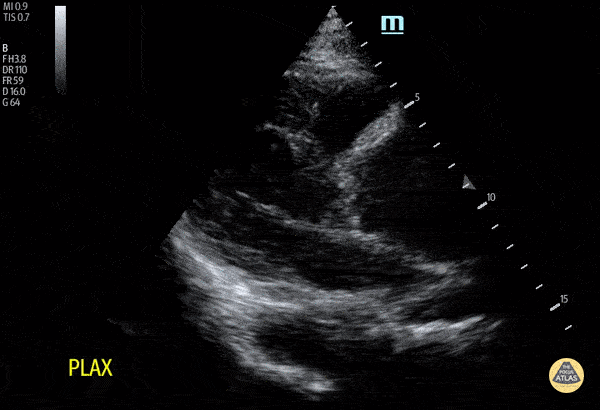

A dilated aortic root in a patient with chest pain radiating to the back. Note that the ratio of right ventricular outflow tract, aortic root and left atrium is not 1:1:1. Whilst you may not always see an intimal flap, a dilated aortic root and new aortic regurgitation may indicate aortic dissection. In this case, aortic dissection was subsequently confirmed on CT aortogram. Dr. Cheng